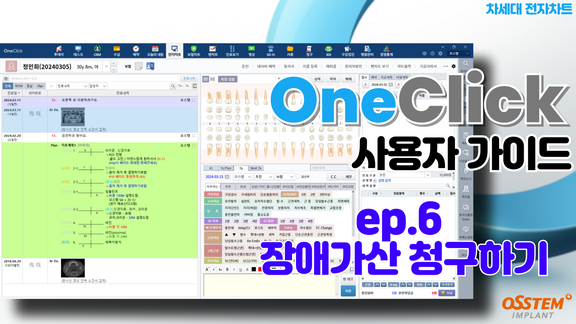

[보험청구]ep6.장애가산 청구

보험부터 전자차트까지

2024-04-19T00:00